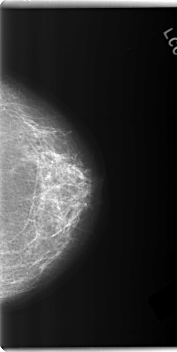

C_0202_1.LEFT_CC

LEFT_CC LINES 5976 PIXELS_PER_LINE 3008 BITS_PER_PIXEL 12 RESOLUTION 50 NON_OVERLAY